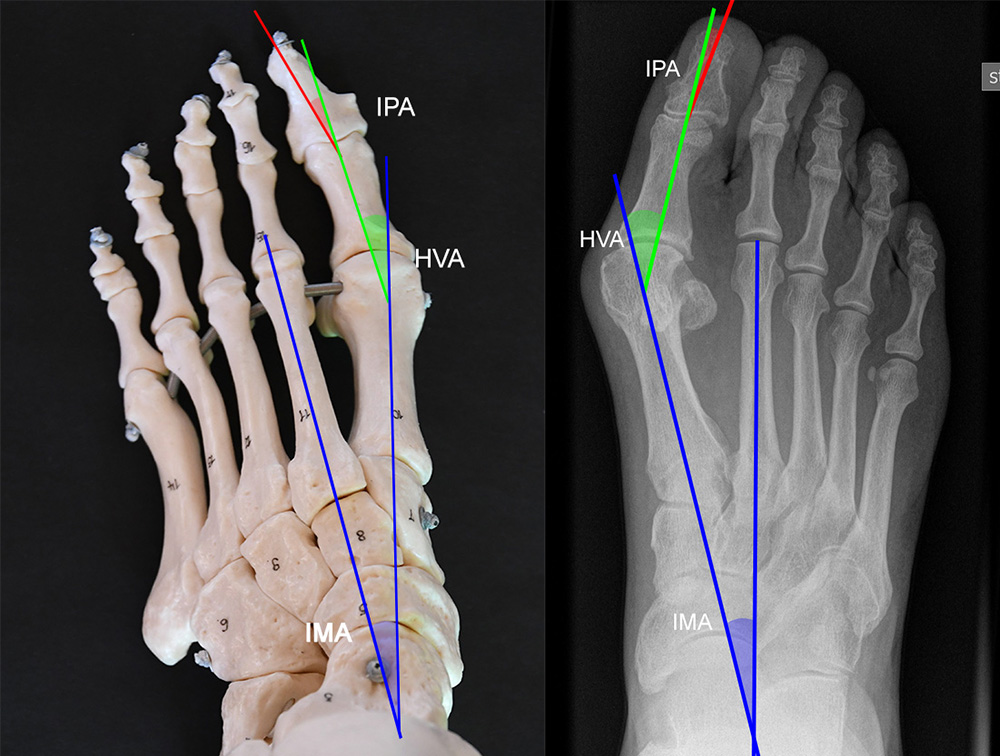

Vermessung der belasteten Aufnahmen des Fußes

Winkelmessungen am Fußskelett beziehen sich sämtlich auf belastete Aufnahmen 6. Die folgenden Aufnahmen zeigen die üblicherweise verwendeten Winkelmaße und ihre Definition. Viele Fehlstellungen des Fußes betreffen den Vor- und Rückfuß. Dies sollte bei der Beurteilung der Bilder und der Therapieplanung stets berücksichtigt werden.

Beurteilung von Fehlstellungen des Vorfußes

Zur Vollansicht und zum Lesen der Bildbeschreibung bitte die Bilder anklicken.

Beurteilung eines Metatarsus adductus

Medial wird eine Linie von der medialen Begrenzung des TMT1-Gelenks und der medialen Begrenzung des Talonavikulargelenks (TN) gezeichnet. Auf der lateralen Seite des Fußes wird eine zweite Linie von der lateralen Begrenzung des Calcaneocuboid-Gelenks (CC) zur lateralen Begrenzung des TMT5-Gelenks gezeichnet. Die Mittelpunkte beiden Linien werden verbunden (blau). Der Winkel zwischen der Achse des Os metatarsale II (rot) und dem Lot auf Verbindungslinie (grün) ist ein Maß für die Stellung des Vorfußes zur Fußwurzel. Dieser Wert dient zur Charakterisierung eines Pes adductus. Ein Pes adductus kann zu einem normwertigem Intermetatarsale I/II Winkel führen, obwohl klinisch eine ausgeprägte Hallux valgus Deformität vorliegt 8. (Norm: ±13° 9.